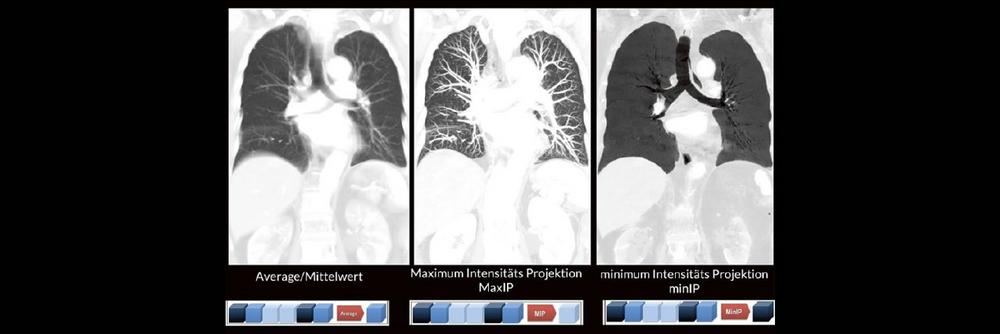

Bildnachverarbeitung in der CT (Webinar | Online)

Alex Riemer Moderne CT-Scanner unterstützen die Anwenderinnen und Anwender bei der Durchführung der meisten CT-Untersuchungen. Hierzu zählt auch das automatische Erstellen von streng coronalen und sagittalen Multiplanaren Reformatierungen (MPR´s).  Es gibt jedoch CT-Untersuchungen, bei denen die MPR´s individuell an die Anatomie angepasst werden müssen. Doch gerade bei diesen Bildnachverarbeitungen gibt es oft Unsicherheiten darüber, worauf […]